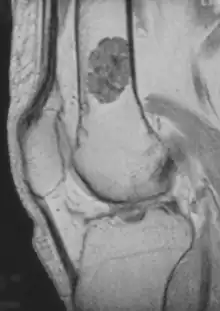

MRI T1 showing an enchondroma in the femur.

• magnetic resonance imaging (MRI)[7] – a diagnostic procedure that uses a combination of large magnets, radiofrequencies, and a computer to produce detailed images of organs and structures within the body. This test is done to rule out any associated abnormalities of the spinal cord and nerves.